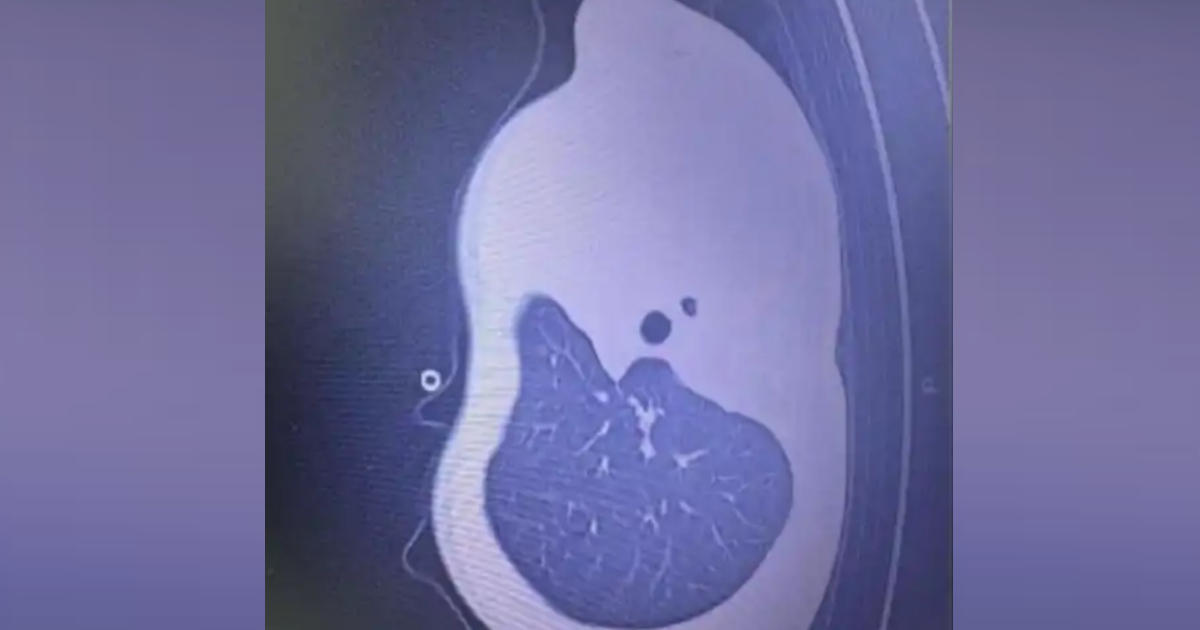

12月2日早上,小宇呼吸急促、嘴唇發紫、精神不振,家人急忙將他送到浙江大學醫學院附屬兒童醫院急診。經檢查,驗血顯示炎症指標大幅上升,胸片更發現左側肺葉幾乎「不工作了,影像中變成大片白色」,就是所說的「白肺」。

浙江大學醫學院附屬兒童醫院PICU副主任楊子浩主任醫師表示,這是流感合併細菌感染引起的嚴重肺炎,同時發生壞死性喉氣管支氣管炎,一種嚴重併發症:黏稠痰栓會像樹枝一樣堵在氣道分支處,導致肺部無法正常通氣,若不及時處理,幾小時就可能威脅生命。

當天中午,小宇被緊急送進PICU。下午4點多,醫生做了氣管鏡,鏡下畫面比預期的還要嚴重:氣道裡堵滿了樹枝狀的黏稠痰栓,呼吸通道完全被塞住,氣道內壁還有壞死組織。